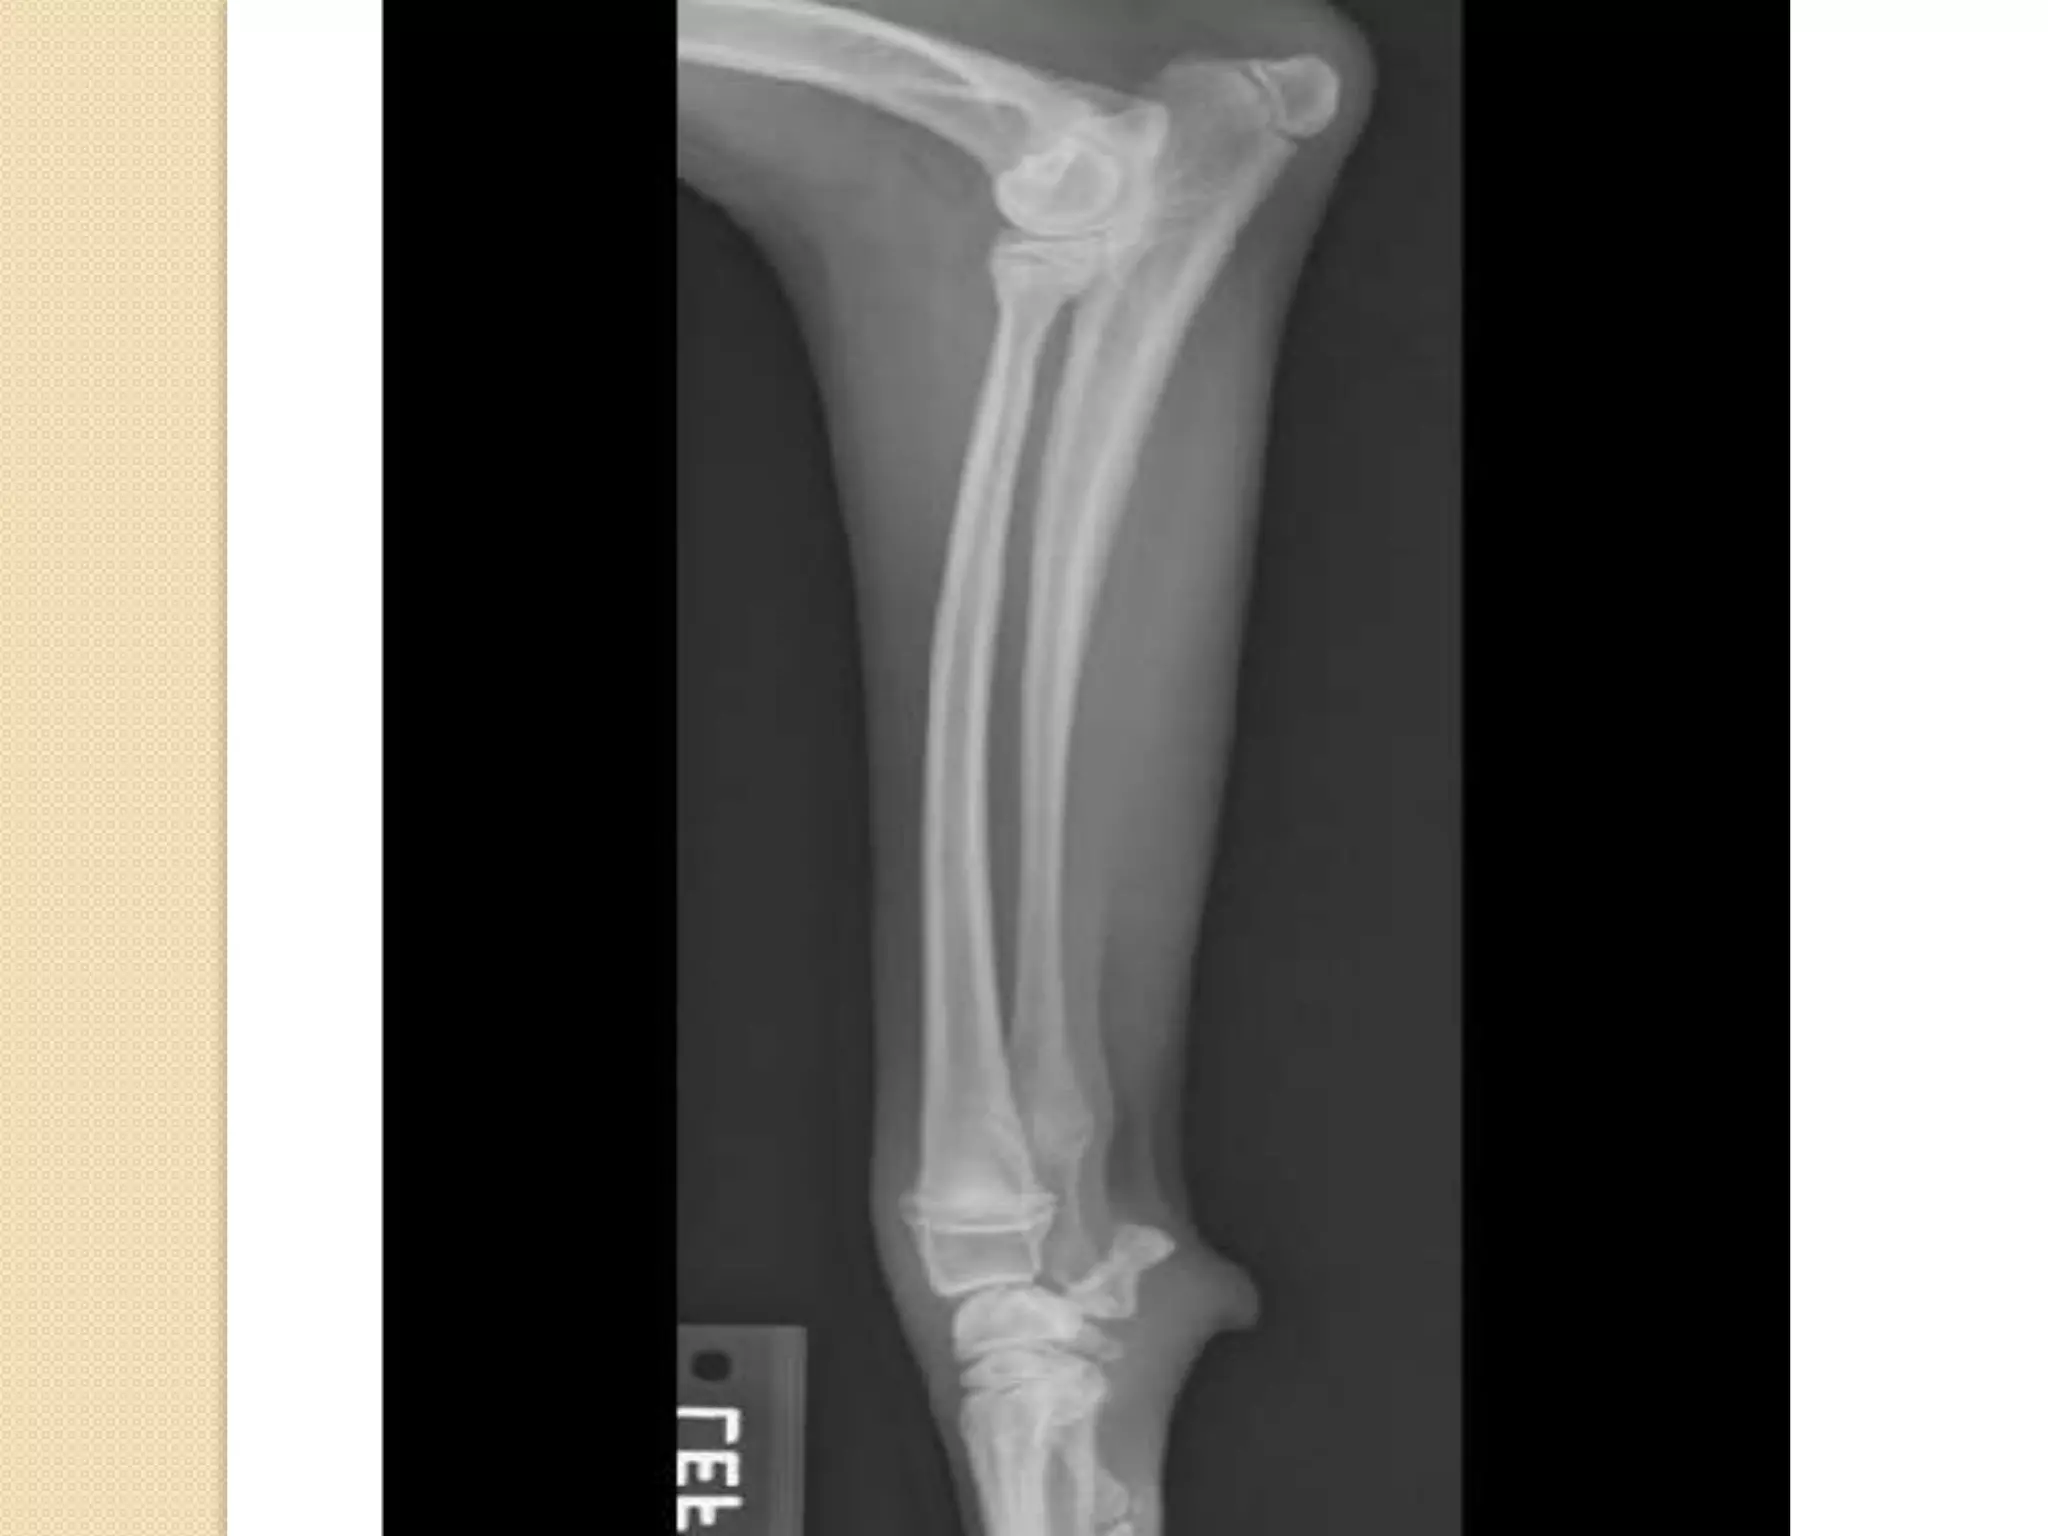

Fibula , tibia and patella :

B= tibia

C= fibula

D = Patella

The fibula (B) is lateral to

the tibia (A), and the tibial

tuberocity (C) and tibial

crest (D) are on the cranial

aspect of the tibia. This

means that image one is a

cranial view and image two is

a lateral view of the left

tibia and fibula.

The tibial tuberosity is on

the proximal aspect of the

tibia

Fibula , tibiaand patella : B= tibia C= fibula D = Patella

• 77.

The fibula (B)is lateral to the tibia (A), and the tibial tuberocity (C) and tibial crest (D) are on the cranial aspect of the tibia. This means that image one is a cranial view and image two is a lateral view of the left tibia and fibula. The tibial tuberosity is on the proximal aspect of the tibia